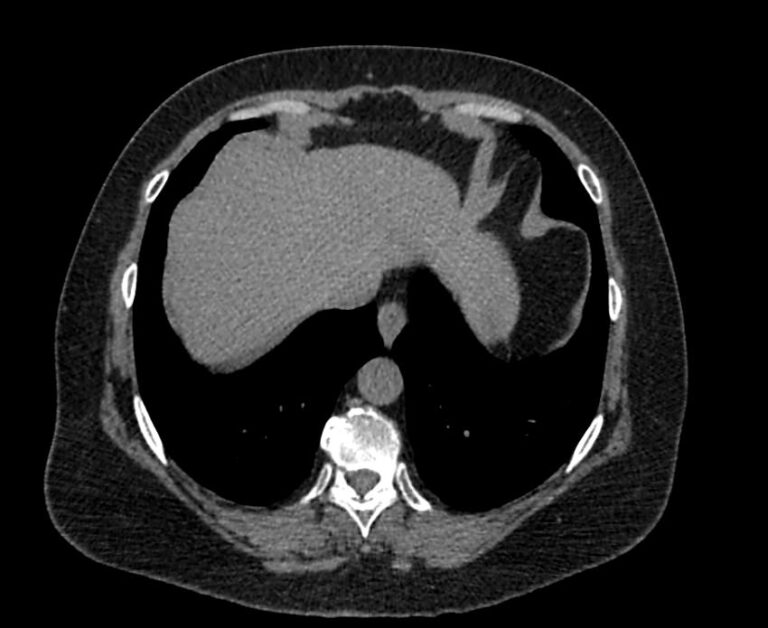

Мультиспиральная компьютерная томография (МСКТ) брюшной полости относится к современным лучевым методам исследования, с помощью которого можно оценить состояние органов брюшной полости (печени, желчного пузыря, поджелудочной железы, селезенки), прилегающих к ним кровеносных сосудов и лимфатических узлов.

С помощью мультиспиральной компьютерной томографии проводятся послойные рентгеновские снимки исследуемой области с толщиной среза от 0,5 мм. В нашей клинике исследование выполняется на компьютерном томографе экспертного класса TOSHIBA AQUILION CXL, который оснащен 128 детекторами, позволяющими получать за несколько секунд снимки брюшной полости с высокой точностью. Большое количество детекторов позволяет получить точные данные, при этом сократить время исследования и сделать минимальной лучевую нагрузку на пациента. Кроме того, инновационные технологии аппарата дают возможность сформировать объемную модель органа и окружающих структур, что также способствует проведению точной и достоверной диагностики.

При подозрении на опухоли, воспалительные процессы, гнойные очаги назначается КТ брюшной полости с внутривенным болюсным контрастированием. Для этого пациенту внутривенно вводится рентгеноконтрастное вещество на основе йода. Благодаря усиленному кровоснабжению препарат накапливается в структуре патологических образований и помогает врачу-рентгенологу выявить изменения в структуре внутренних органов.

Метод контрастирования помогает максимально точно выявить очаг патологии уже на начальной стадии, а также установить его локализацию, точные размеры, форму и особенности кровоснабжения.